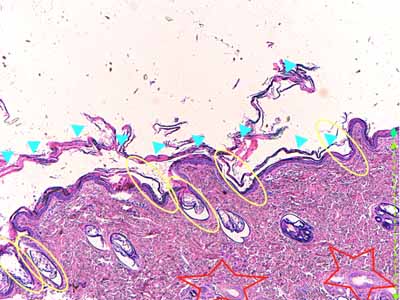

Photo 2 (Hémalun Eosine X 40) : L’épiderme est le siège d’une hyperkératose orthokératosique

laminée parfois compactée, intéressant également les ostia folliculaires. Le derme semble silencieux.

Légendes de la Photo 2 :

- Pointe de flèche turquoise : hyperkératose orthokératosique

- Ovales jaunes : ostia folliculaires hyperkératosiques

- Étoiles rouges : unités annexielles folliculo-sébacées

- Double pointe de flèche verte : épaisseur épidermique

- Double flèche pointillée verte : épaisseur dermique